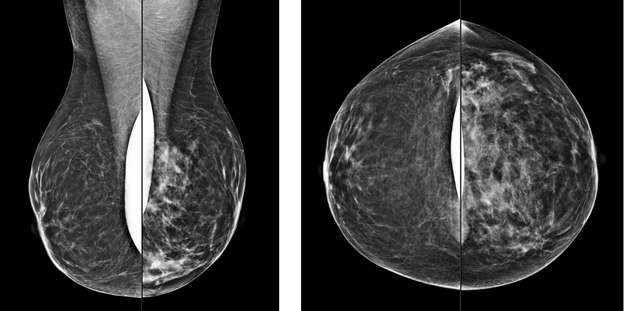

Developing Asymmetry:

A developing asymmetry is an asymmetry that is larger or more conspicuous compared to prior exams3. Since breast tissue tends to become less dense with age, developing asymmetries are usually more concerning and may warrant additional workup such as biopsies.

Serial MLO view of the left breast (from oldest to newest) demonstrate increase density in the left superior breast consistent with a developing asymmetry. This particular case turned out to be biopsy-proven pseudoangiomatous stromal hyperplasia.